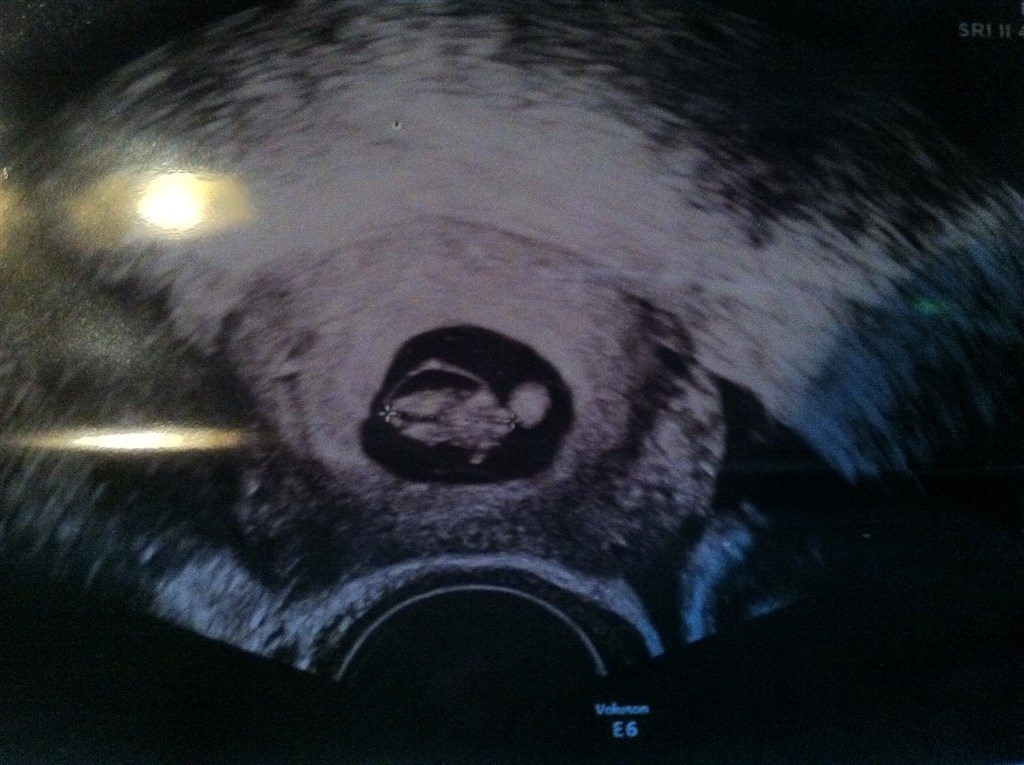

Vi var til en tidlig tryghedsscanning i uge 5 (vi troede jeg var i uge 8), der var også et lille twist, nemlig endnu en blommesæk, og 2 stk bankende hjerter :-) foreskel var der dog præcis som dine og vi skulle også komme tilbage ugen efter. Målene var 2.2 mm og 7.7mm. De var enæggede kunne ee allerede se der. Har i fået noget at vide ang det?

Har lagt et billede med af vores første scanning